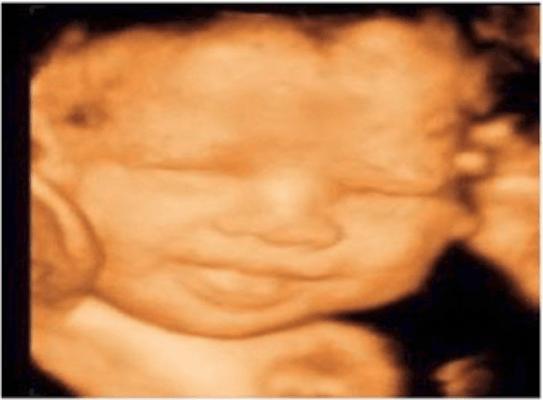

3D Imaging Services

Photos

3D Imaging Services is a leading provider of cutting-edge imaging solutions in New York, NY. With a focus on delivering high-quality results, they offer a wide range of services and expertise in the field of 3D imaging.